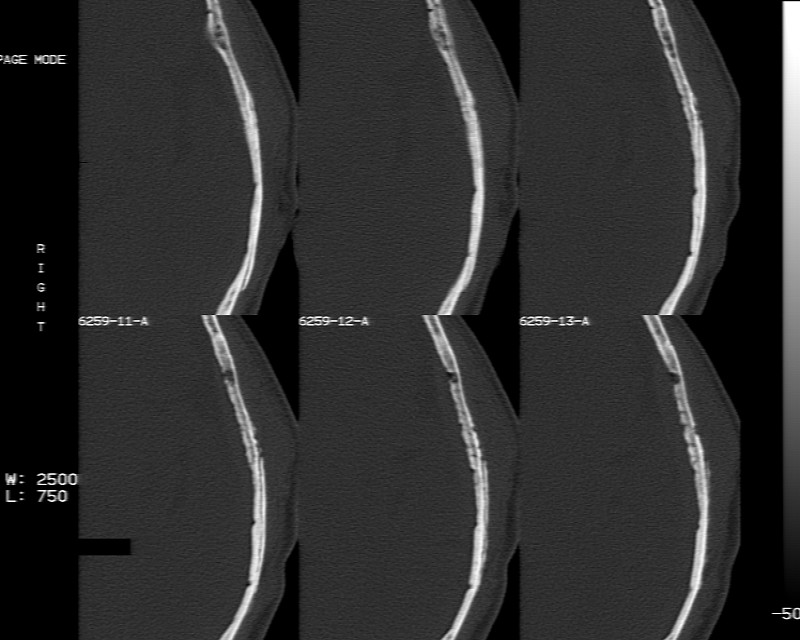

m70y, 2个月前发现左颞部有'包'隆起,近来自觉增大,无外伤无任何不适症状而就医,触诊包块质地较硬无移动无波动无皮温升高,胸片示右上肺陈旧结核....,ct扫描见左颞骨翼板局部内外骨板骨质破坏,似筛孔状,外板侧有骨膜线状增生,伴局部软组织丘状肿块,内板下梭形肿胀硬膜增厚翘起......颅内脑无异常.考虑骨良性病变 1.低度骨感染.   2.嗜酸性肉芽肿. 3.不排外骨结核...建议其穿刺活检,但患者失踪,追踪到结果定将公告.请大家分析.

左颞骨内板不光滑,密度减低,内板下可见新月形的软织密度影。脑实质轻度受压,外板外见膨胀形稍高密度影。考虑嗜酸性肉芽肿。建议增强扫描